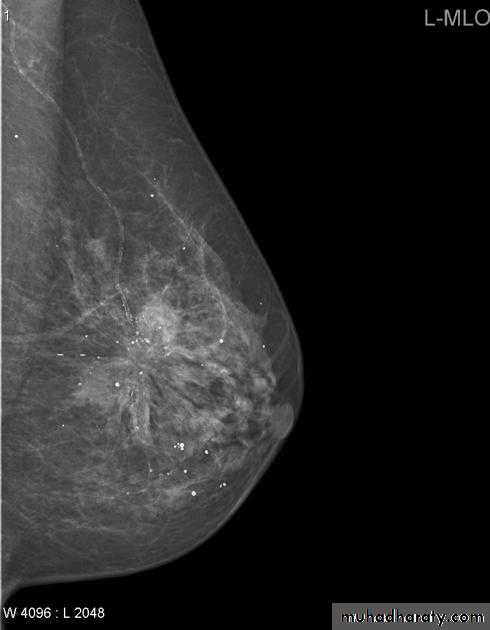

Mammography views

The mediolateral oblique (MLO) view is one of standard mammographic views. It is the most important projection as it allows to depict most breast tissue.

The craniocaudal view (CC view), is one of the two standard projections in a screening mammography. It must show the medial part as well the external lateral portion of the breast as much as possible.